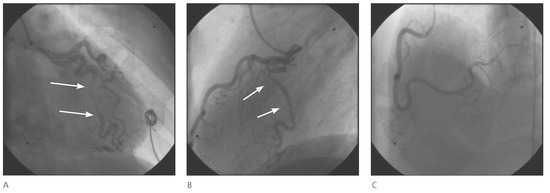

The fact that non-valvular (non-rheumatic) atrial fibrillation creates detectable thrombi in 17% of patients without oral anticoagulation and that 16% of the 17% (over 90% relatively) reside in the left atrial appendage (LAA), suggest that patients w...